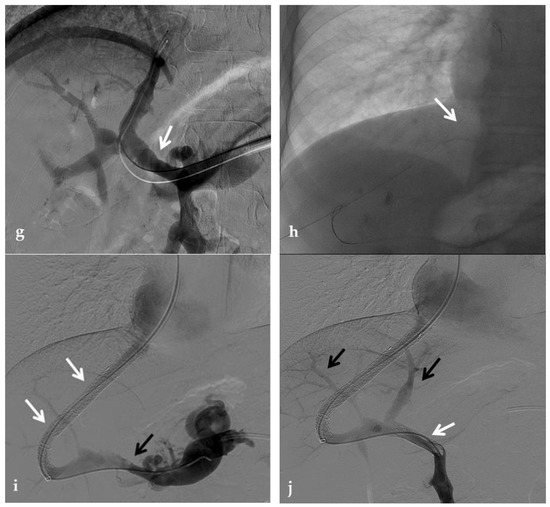

Stenosis and thrombosis of the bypass graft typically occur weeks to years after surgery and may be clinically evident with recurrence of portal hypertension and impaired liver function tests. Thrombosis or high-grade stenosis represents the main cause of bypass graft occlusion. CT may show a low-density cord, representing the occluded bypass. CDUS can show the thrombus with a hypoechoic appearance associated with an absence of portal flow. In these situations, stenosis and thrombosis can be treated with transhepatic, transsplenic, or transmesenteric portography and angioplasty. Balloon dilation can be performed when the transtenotic pressure gradient is greater than 5 mmHg or when a stenosis is radiologically confirmed [66] (Figure 14).

Figure 14.

Anteroposterior view of a percutaneous transsplenic portography imaging series of an occluded Meso-Rex bypass in the same patient of Figure 8. (a) Percutaneous transsplenic portography shows extensive jejunal and gastric varices (arrows), with no opacification of the Meso-Rex bypass. (b) After superior mesenteric vein catheterization, portography shows the portal cavernoma (arrow) with no opacification of the native intrahepatic portal branches (whose patency was documented with retrograde portography in Figure 8). (c) Portography image shows successful recanalization of the mesenteric anastomosis of the Meso-Rex bypass (white arrow), with intrahepatic portal branches opacification (black arrows). (d) X-Ray image shows angioplasty of the bypass performed through a 9-mm non-compliant balloon catheter. During angioplasty, a focal notch (arrow) representing the mesenteric anastomotic stenosis is clearly visible. (e) Portography image acquired after bypass recanalization and angioplasty shows regular opacification of the intrahepatic portal system (arrows). (f) Portography image from the superior mesenteric vein shows a re-expanded Meso-Rex bypass with complete opacification in the mesenteric anastomotic tract (arrow). The intrahepatic portal system is regularly represented; the portal cavernoma and gastro-jejunal varices disappeared.